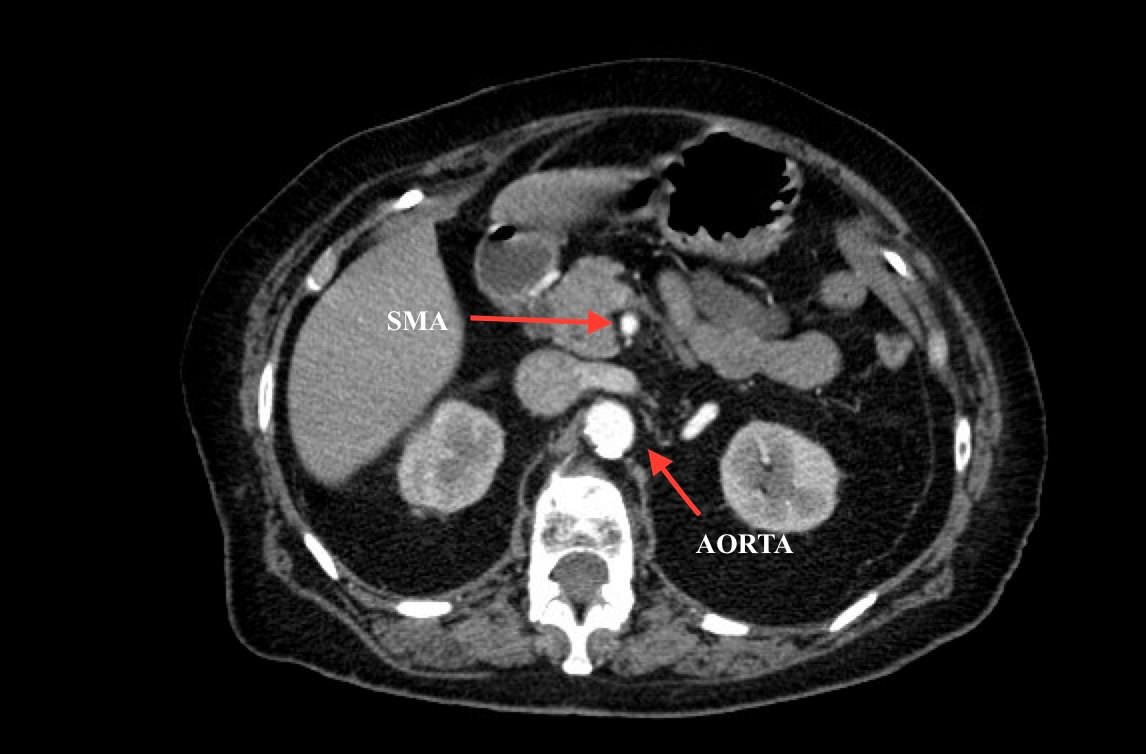

Computed tomography (CT) angiogram of the abdomen and pelvis revealed a superior mesenteric artery (SMA) thrombosis 5 cm from the origin off of the abdominal aorta. As seen in the sagittal view, there does not appear to be any contrast 5 cm past the origin of the SMA. On the axial views, you can trace the SMA until the point that there is no longer any contrast visible which indicates the start of the thrombus. The SMA does not appear to be reconstituted. There was normal flow to the celiac artery. (See annotated images).